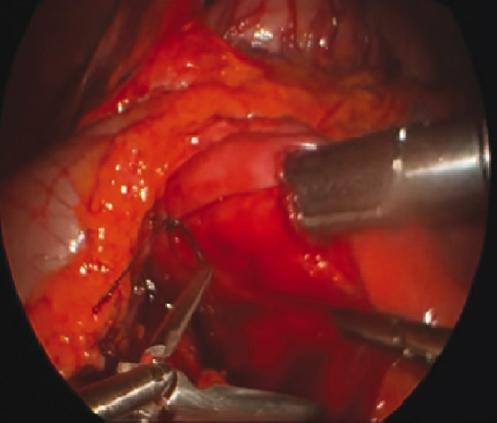

The patient was taken to the operating room for a laparoscopic duodenojejunostomy. The proximal duodenum was dilated while the jejunum appeared to be normal. A Kocher maneuver was performed, revealing no pancreatic or duodenal masses. The ligament of Treitz was identified, and a portion of jejunum approximately 20 cm distal to the ligament of Treitz was found to easily reach the duodenum. A silk suture was placed between the duodenum and jejunum, acting as a bridge of these two portions of the bowel. A duodenotomy was made in the lateral aspect of the second portion of the duodenum avoiding the ampulla. An antimesenteric jejunotomy is made in a similar way with electrocautery and then a 60 mm laparoscopic linear stapling device was used to create a side-to-side anastomosis (duodenojejunostomy) (Fig. 3). The common enterotomy was closed using a running 2-0 PDS suture in a single layer. A reinforcement suture was placed at the apex of the anastomosis. Intraoperative endoscopy was performed to evaluate the anastomosis and then air leak test was negative. There was no need for placing drains or nasogastric tube. The patient did well following surgery, she was gradually advanced to a soft diet and was discharged home on post-operative day 5 without complications.